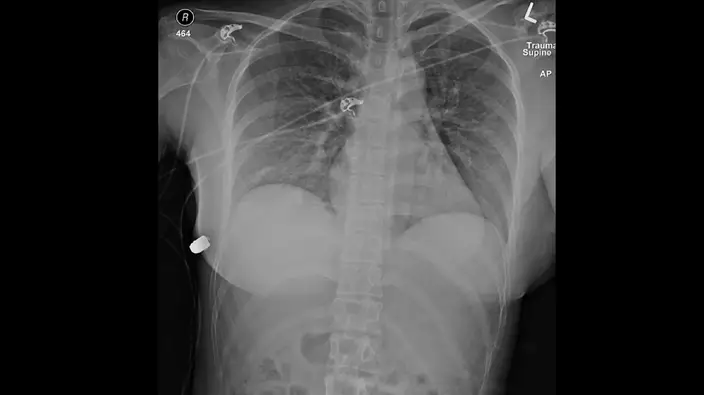

加拿大多倫多一名30歲女子約兩年前因為胸部中彈,如今該案件又重新受到外界關注,根據上周SAGE醫學雜誌發表的案例研究中,該名女子隆胸的矽膠可能讓子彈偏離心臟,成功挽救她的性命,醫生表示,這是第一個納入醫學文獻的個案中因矽膠植入物救回病人性命的案例。

事發當時這名女子正在街上行走,突然感覺到左胸發熱、伴隨疼痛感,她一看發現身上有血,於是自行前往急症室尋求幫助,根據外媒報導,子彈從左邊乳房進入,停留在身體右邊;右邊肋骨骨折,左乳植入的矽膠受損,醫生認為子彈從左胸「轉彎」到右胸。

外科醫生麥克維納(Giancarlo McEvenue)表示,當時該女子進入急症室時還在講話,胸部的植入物讓子彈偏離軌道,「左側是心臟和肺部,如果子彈進入胸部,那麼她將遭受更嚴重、甚至危及生命的傷害」。

美國合法使用的隆乳植入物有兩種,都是矽膠外層,其中一種是鹽水填充、另一種則是矽膠填充,先前有研究指出,鹽水填充物會減慢子彈速度;而另一項研究則詳細介紹矽膠填充物如何阻止子彈造成的傷害。